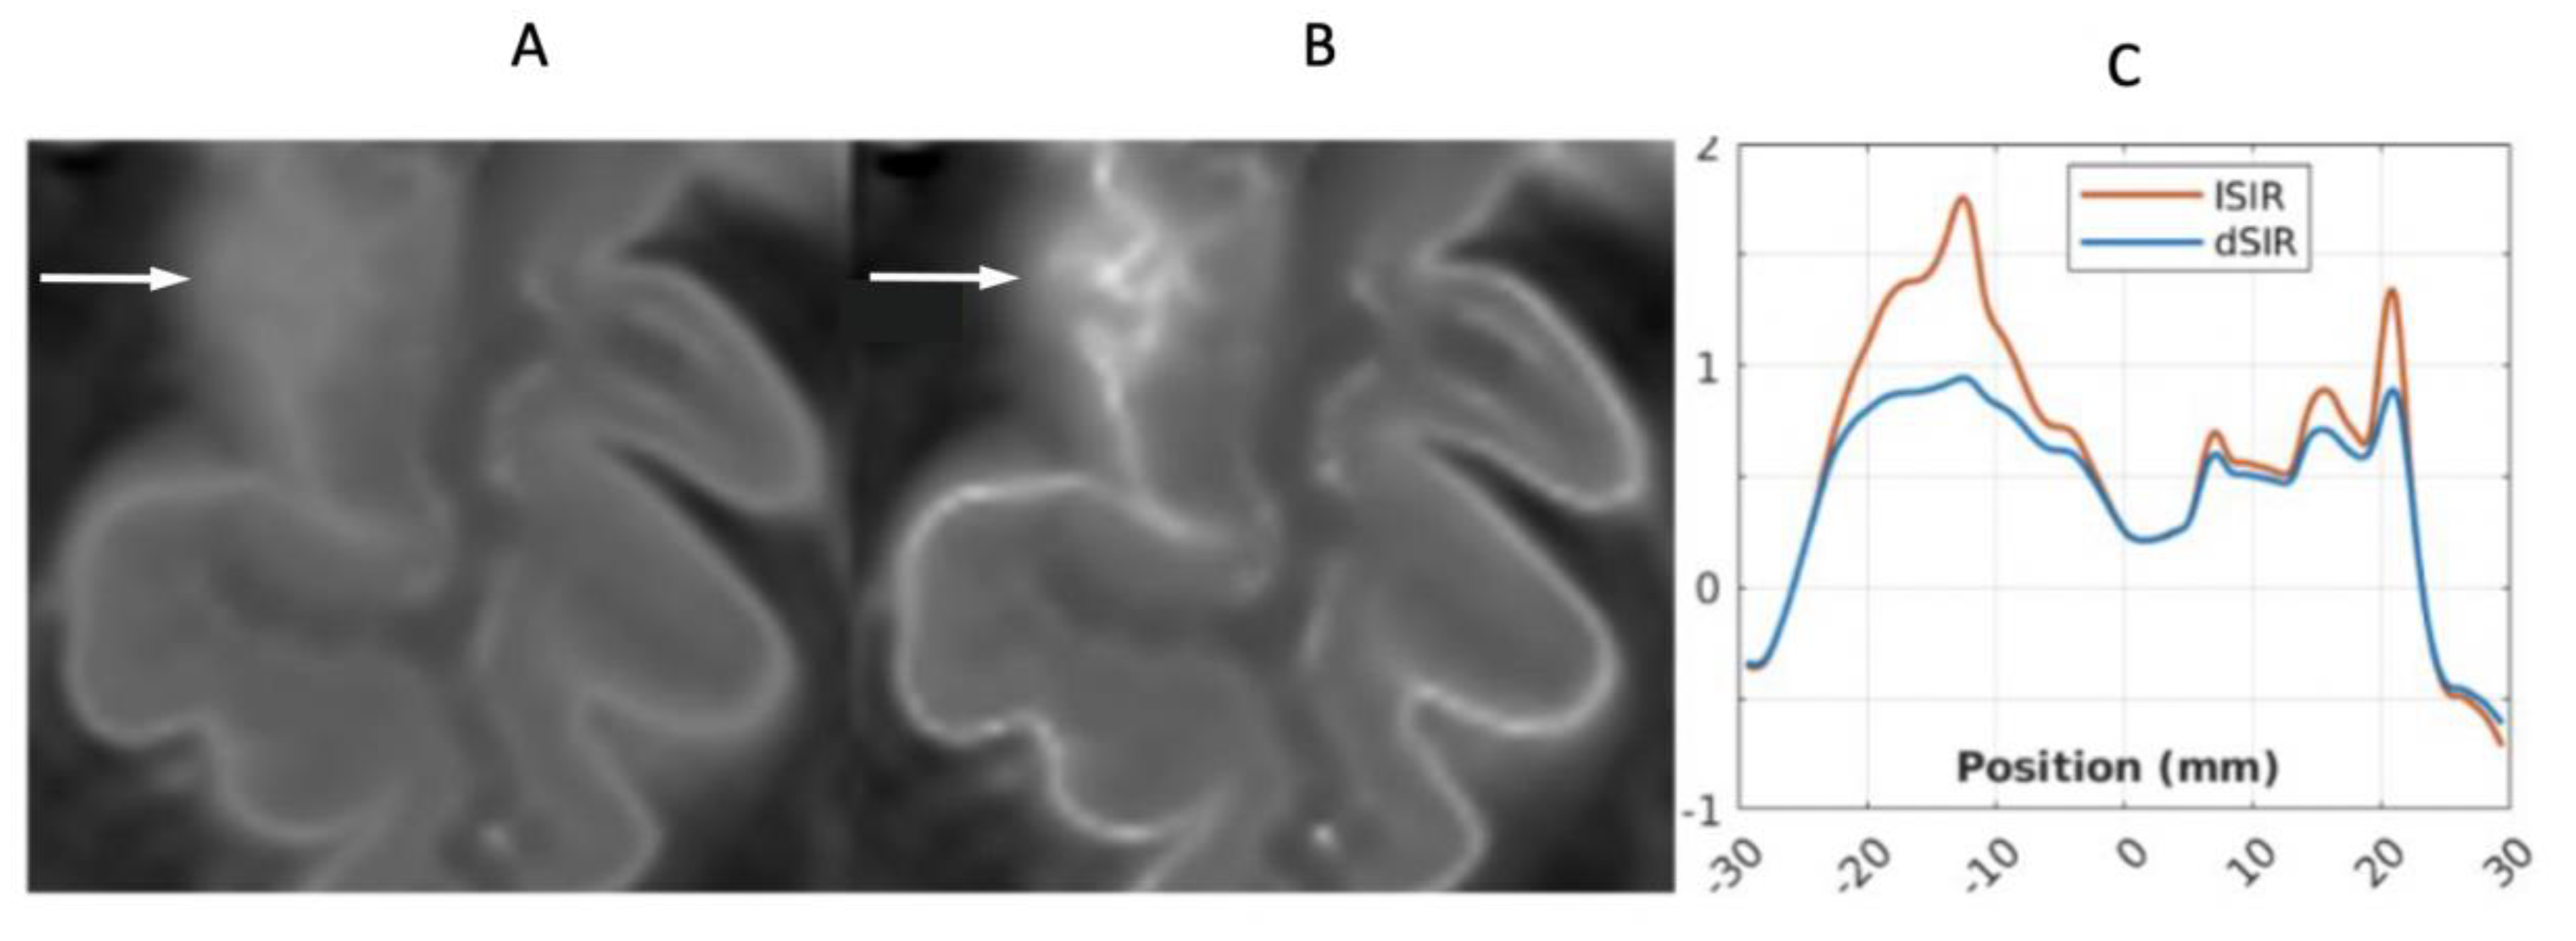

Figure 23.

41-year-old female patient with MS. A leukocortical lesion in the right medial frontal region is shown on the narrow mD dSIR (T1-BLAIR) image (A) and a matching lSIR image (B) (arrows). There are also left to right profiles with signal plotted against position (in mm) for the dSIR (blue) and lSIR (orange) images (C) at the level of the horizontal arrows shown in (A) and (B). No boundary between white matter and gray matter is seen within the lesion in (A). A disrupted high signal boundary between white matter and gray matter is seen in the lesion in (B). The lSIR profile (orange) has higher signal and steeper slopes than the dSIR profile (blue) in (C). The difference in signal (or contrast) achieved for the same change in position is generally greater with the lSIR filter i.e., the contrast shown on the lSIR image generally has a higher spatial resolution.